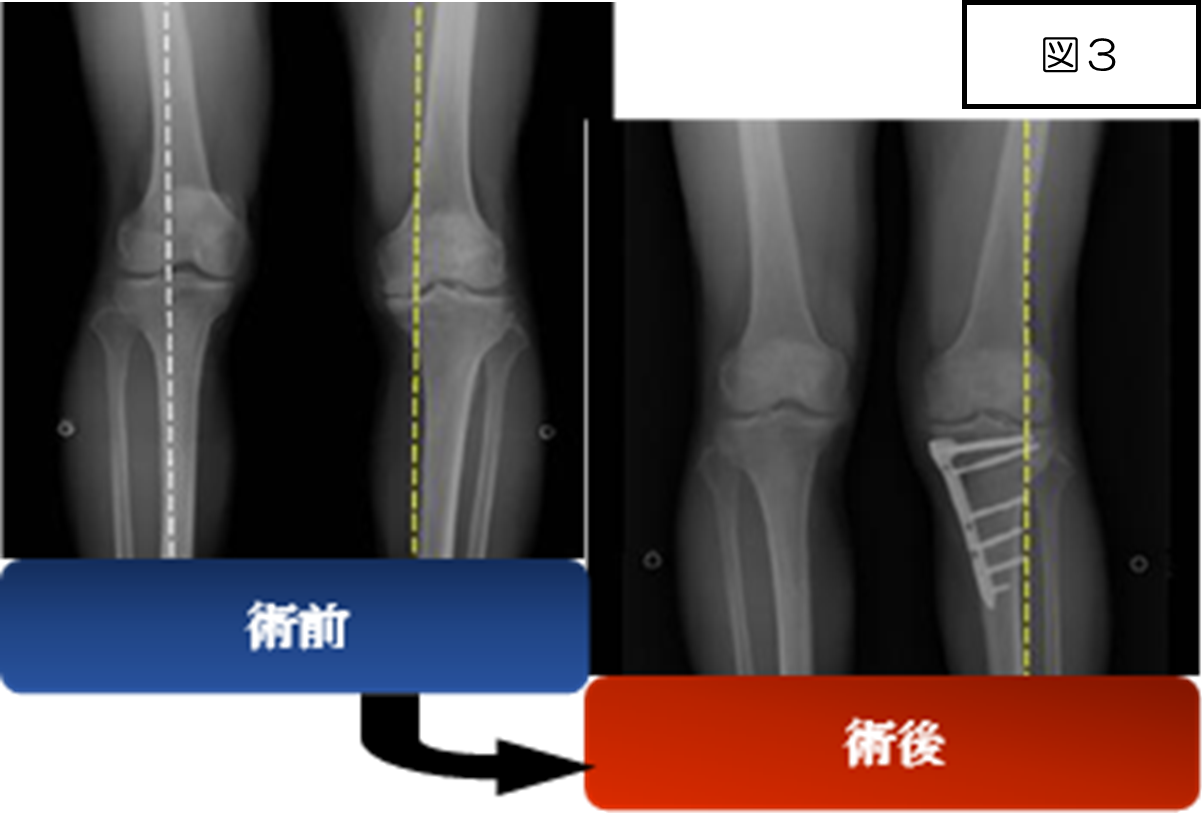

膝骨切り術

O脚による変形性関節症の悪化を防ぐ目的で、脛骨(すねの骨)を切ってプレート(チタン製の板とスクリュー)で固定する手術です(図3)。脛骨を切ったのち、人工骨を使用し角度を矯正。そして、比較的正常な軟骨が残っている外側へ負荷を移動させます。この手術の一番のメリットは、何と言っても自分の膝関節が温存できることです。人工関節の場合は、正座は不可能となってしまいますが、骨切り術であれば、術後6割程度の方が正座可能です。また、スポーツや肉体労働などへの復帰も可能です。もちろん機能回復には、退院後も筋力強化を目的としたトレーニングを継続する事が大切です。